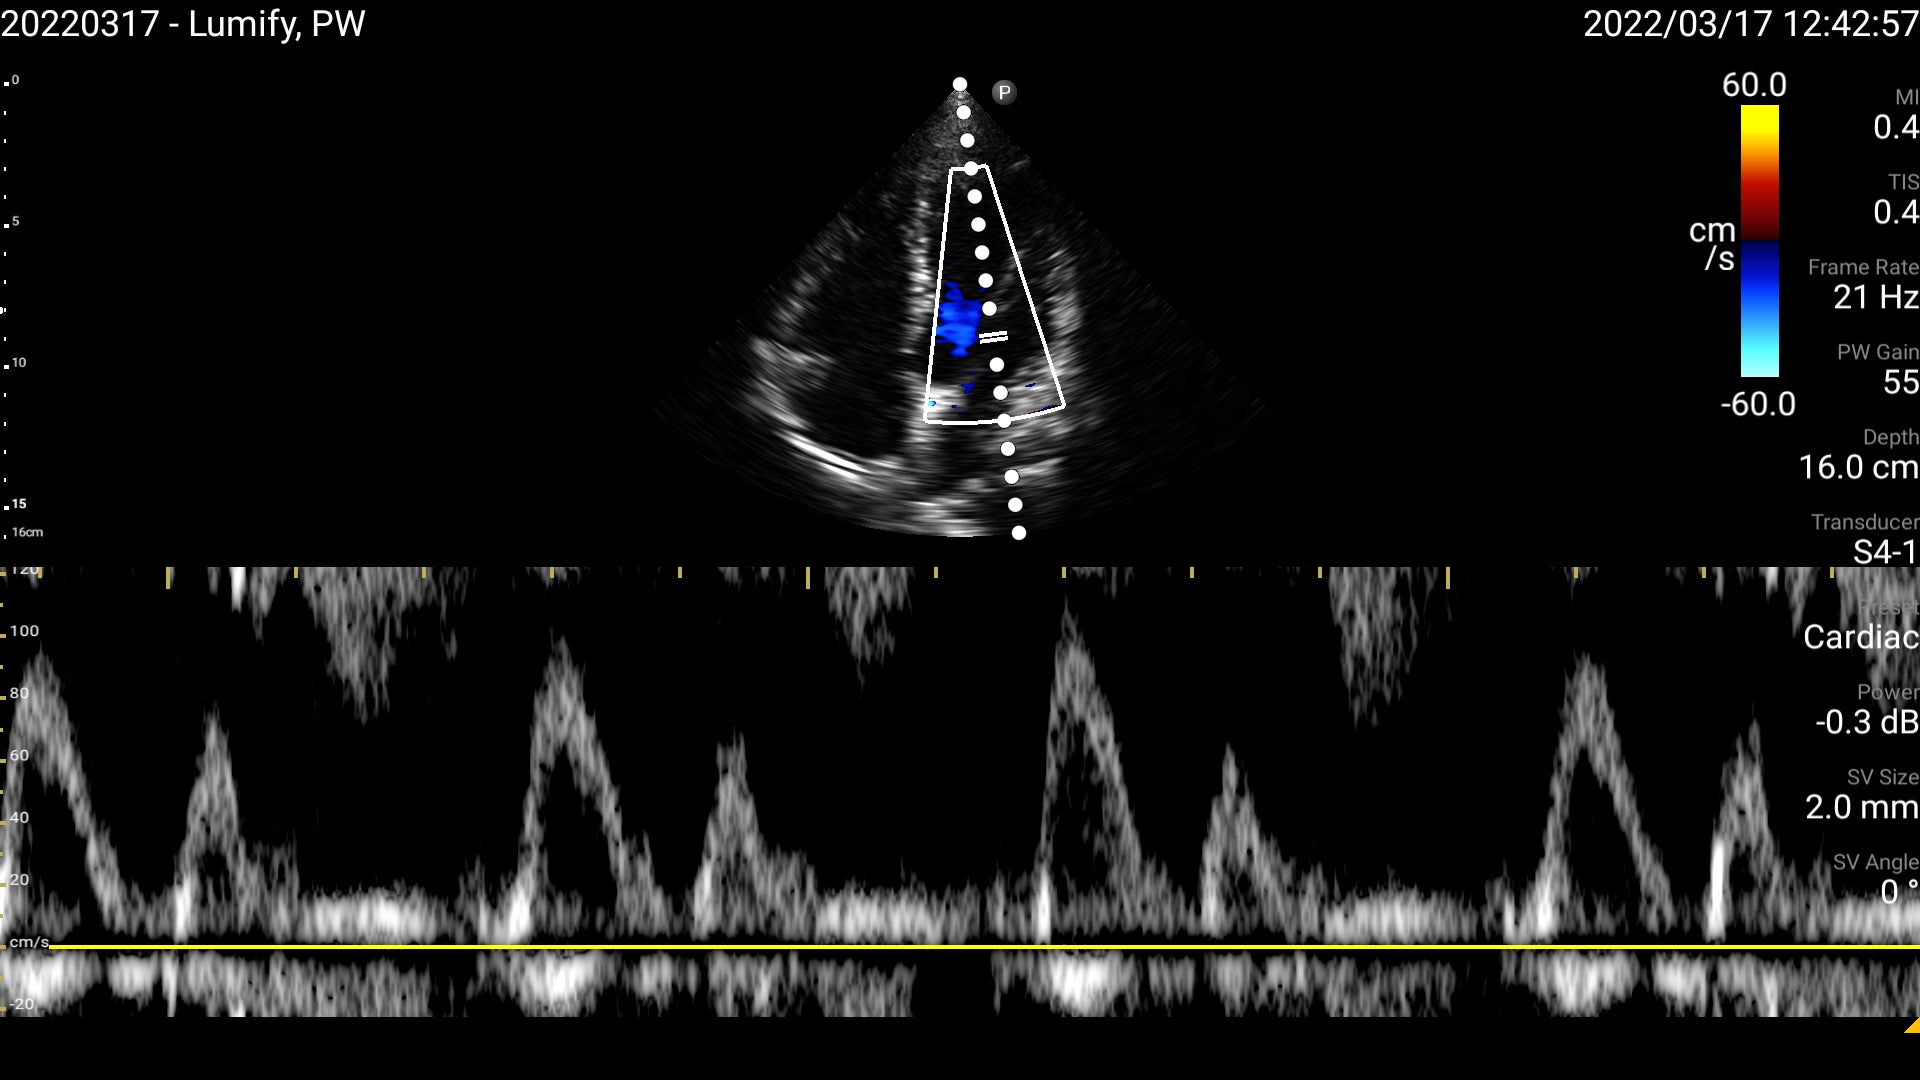

1. パルスドプラ法(血流計測機能)

全てのトランスジューサで、パルスドプラ法による血流の定量評価が可能です。心不全や動脈硬化、バスキュラーアクセスや臍帯血流の評価等に活用できます。さらに自動調整機能により、ワンボタンで波形の最適化が可能です。

パルスドプラ法による僧帽弁血流速度波形(S5-1セクタ・トランスジューサ)